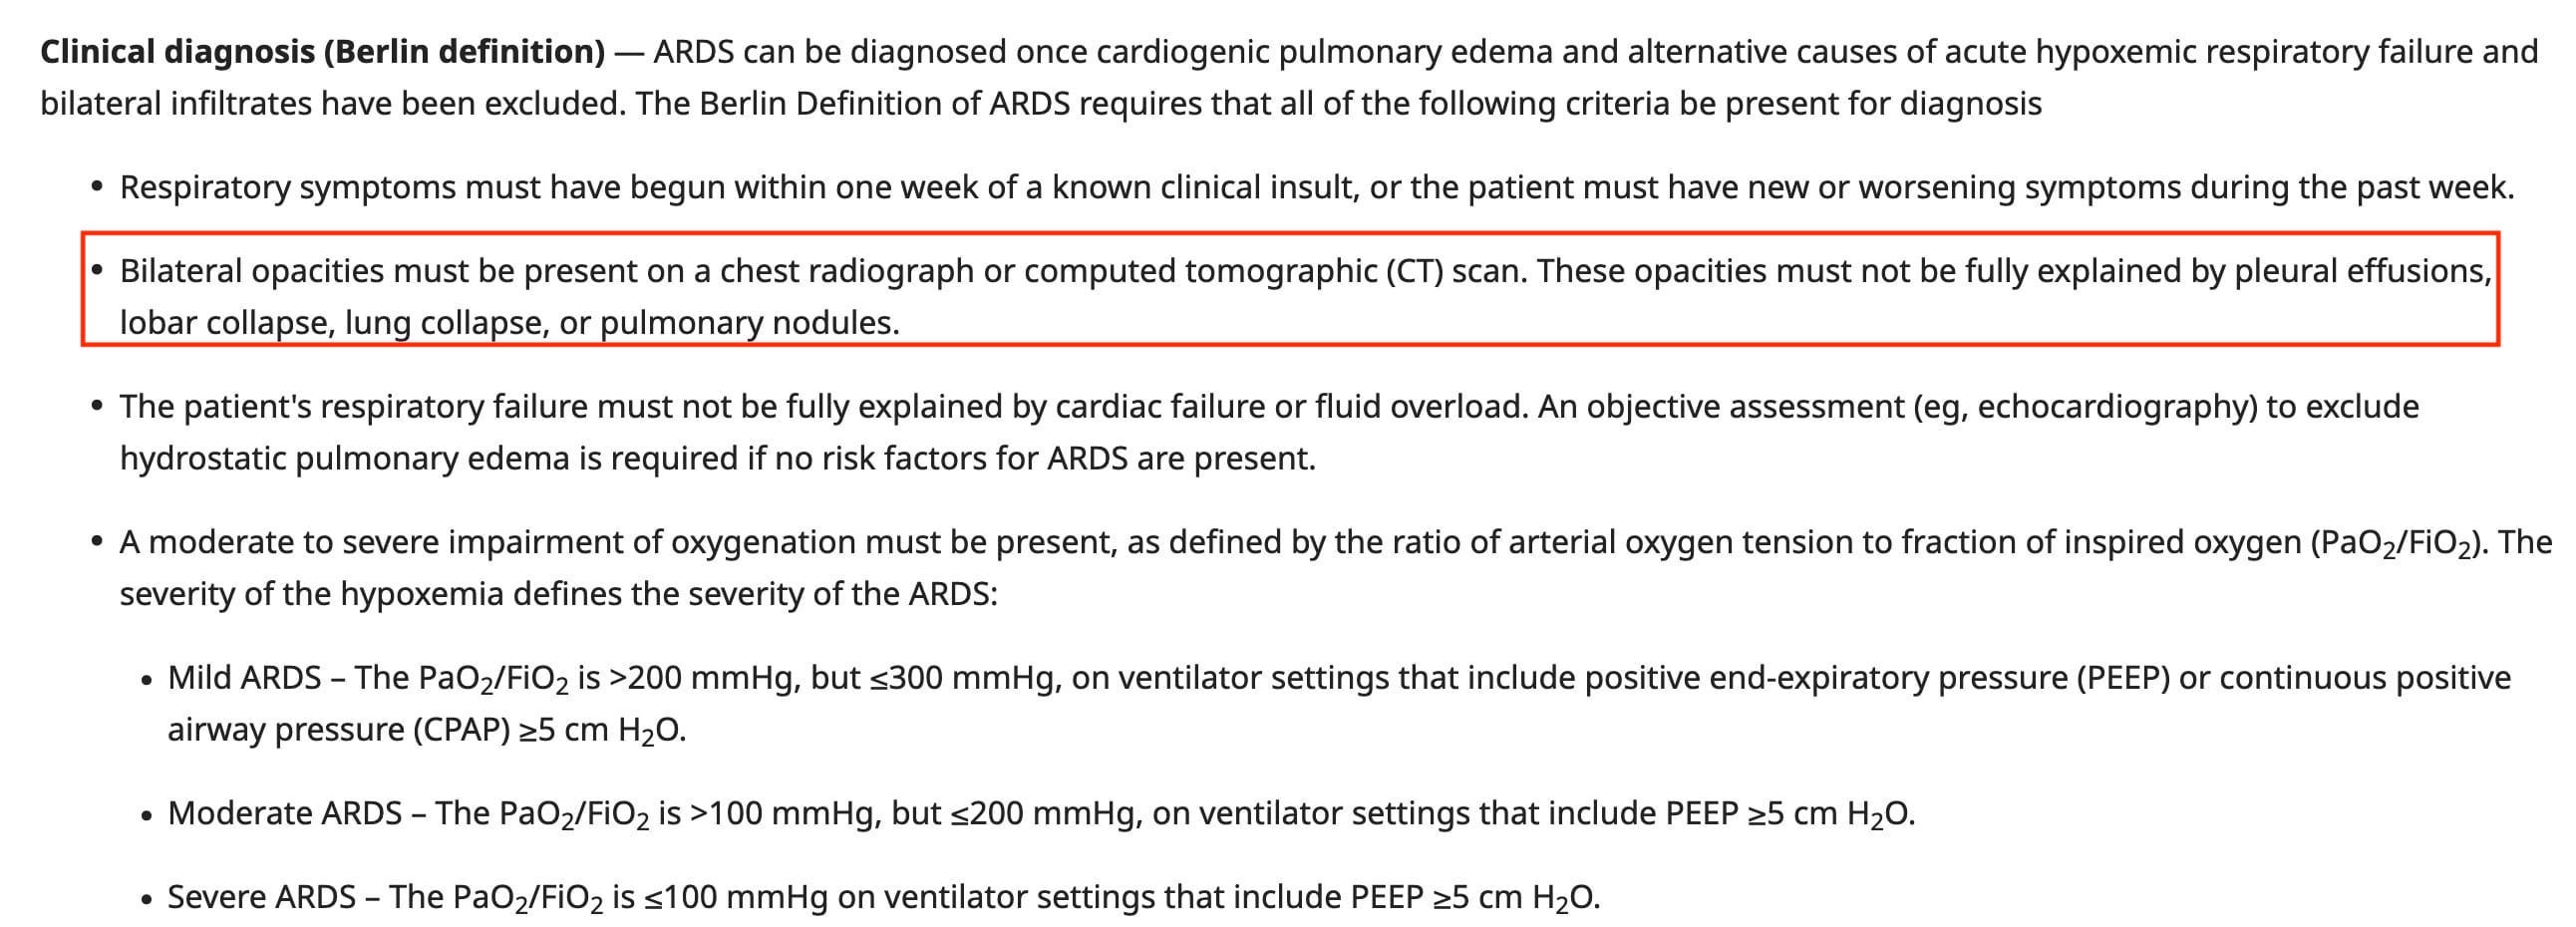

Acute Lung Injury Edema in Acute Respiratory Distress Syndrome

Criteria for the diagnosis of the clinical entity—ARDS—have been revised several times. This excerpt from UpToDate ® is a useful summary.

It’s common to be asked this question by a clinical colleague: “Are the findings consistent with ARDS”? Of course, that’s the wrong question, which should be: “Are the findings consistent with acute lung injury edema?”

Radiologists do not diagnose ARDS, as such!